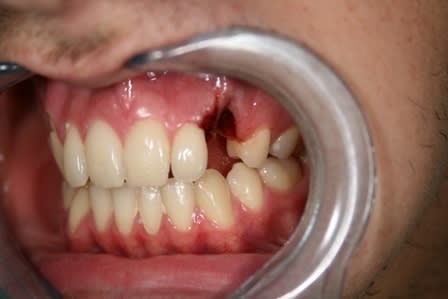

Quelque chose comme cela, qui doit rester souple. Fil fin en alliage nickel-titane et collage résine ou composite.

Patient de 20 ans venu en Urg cette après midi:

dent perdue temps moins de 2h

Suite à appel gardée en bouche

Bio réalisée dans une compresse stérile

Réimplantation après rinçage alvéole sérum Phy

Contention au Ribbond + compo , pas facile quand çà saigne

AB pendant 6 jours + Chx.

J'ai juste un doute en ce qui concerne l'hypochlorite , je ne m'en suis pas servi pour rincer le canal de peur de finir d'achever les quelques fibroblastes présents sur le cément du coup j'ai rincer le canal au sérum phy.

désolé pour l'ordre des photos